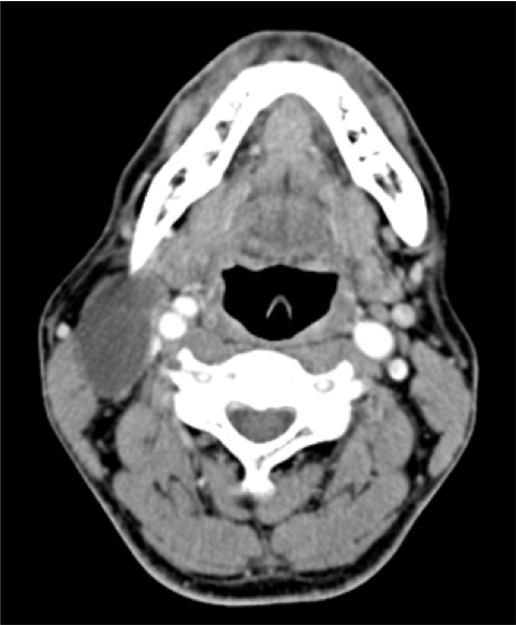

症例7:HPV陽性中咽頭癌、頸部リンパ節転移

頸部造影CT

出典

img

1: 著者提供